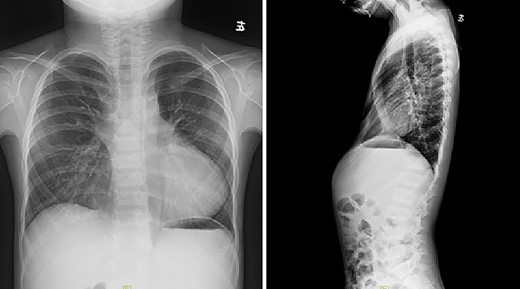

The patient was a 7-year-old boy. Two years ago, he underwent surgical treatment for pectus excavatum in a local hospital. At that time, Wang procedure was used and a steel bar was implanted. After the operation, the steel bar was displaced and the depression recurred (Figs 1 and 2), so the steel bar had to be taken out 1 year after the operation. After removal, his anterior chest wall still had obvious depression, and there was a tendency to aggravate. In order to completely correct the deformity, the patient was recently admitted to our hospital for surgery. Preoperative physical examination showed that the anterior chest wall was asymmetrically depressed, and the deepest depression was located in the right chest wall (Fig. 3). There was a scar in the middle of the anterior chest wall (Fig. 3). Preoperative imaging examination showed that the anterior chest wall was depressed, the heart was obviously compressed and moved to the left (Fig. 4). The operation was performed under general anesthesia. Supine position was adopted, with abduction of both upper limbs. Two incisions were made on both lateral chest wall respectively, which were located at the deepest plane of the depression. The muscles were dissected to expose the ribs in the incision. The depression was eliminated by Wung procedure, which was performed as follows [2]: A tunnel at the deepest plane of the depression was made. A special guider was inserted directly through the gap between the sternum and the heart, and then a steel bar introducing tube was connected with the guider. After the introducing tube was pulled into the body by the guider, a special steel bar was pulled by the introducing tube to the bottom of the depression. After the steel bar was rotated, the depression was supported, but the left chest wall began to be protrusive. In order to make the anterior chest wall more beautiful, Wenlin procedure was performed next [3, 4]. An incision at the median scar was made, and a tunnel was built from the median incision to the incision on both sides, which was located between the bone structures and the chest wall muscles. The second steel bar was inserted into the tunnel. After the protrusive part of the anterior chest wall was pressed with the middle part of the steel bar, both sides of the bar was fixed to the ribs on the lateral chest wall. Drainage tubes were placed in the thoracic cavity on both sides, the incision was closed, and the operation was completed (Fig. 5). No complications occurred during the operation. The total operation time was 50 min and the intraoperative bleeding volume was 5 ml. Postoperative X-ray examination showed that the positions of the steel bars were satisfactory and the shape of the chest wall was basically normal (Fig. 6). The patient was discharged 5 days after operation. Follow up for 1 month showed no change in thoracic shape and no discomfort.